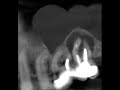

Пульпотомия зуба 8.4 в условиях общего обезболивания